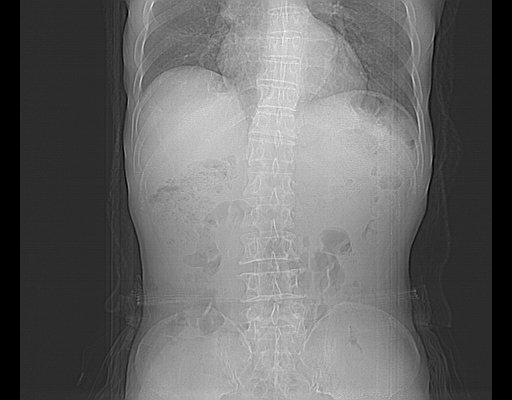

平扫

考虑右肾盂癌,肾动脉受侵,右肾功能减退,右肾盂输尿管积水,管壁增厚,考虑种植转移,应该把下面扫完的

支持右侧肾盂癌伴肾静脉瘤栓形成可能性大,右肾结石.肝右叶后段低密度影,不除外转移.

考虑右肾盂癌,肾动脉受侵,右肾功能减退,右肾盂输尿管积水,管壁增厚,考虑种植转移  支持

右肾盂旁ca并肾静脉瘤栓形成/肾功能降低。

右肾结石。

右肾盂癌,肾动脉受侵,右肾盂输尿管积水,管壁增厚,考虑种植转移

支持 右侧肾盂癌伴肾静脉瘤栓形成可能性大,右肾结石;肝右叶后段低密度影,不除外转移。

1.右侧肾盂癌伴肾盂积水。

2.肾脏功能减退,原因有:(1)肾动脉受侵。(2)肾静脉受侵(3)肾积水,等。本例,肾动脉显影较好,但受压明显;肾静脉无明显显示,受压或静脉癌栓,下腔静脉腔内未见明显充盈缺损。

3.右侧上段输尿管扩张,原因:(1)积水所致;(2)种植。